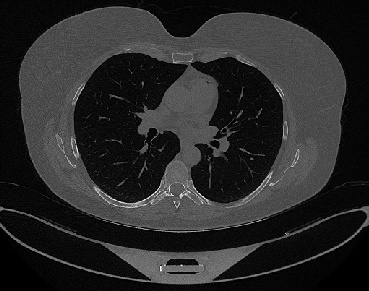

Figure 1 shows four CT scan slices, two from a non-COVID-19 CT scan, on the left and two from a COVID-19 scan, on the right. Bilateral ground glass regions are seen especially in lower lung lobes in the COVID-19 slices.